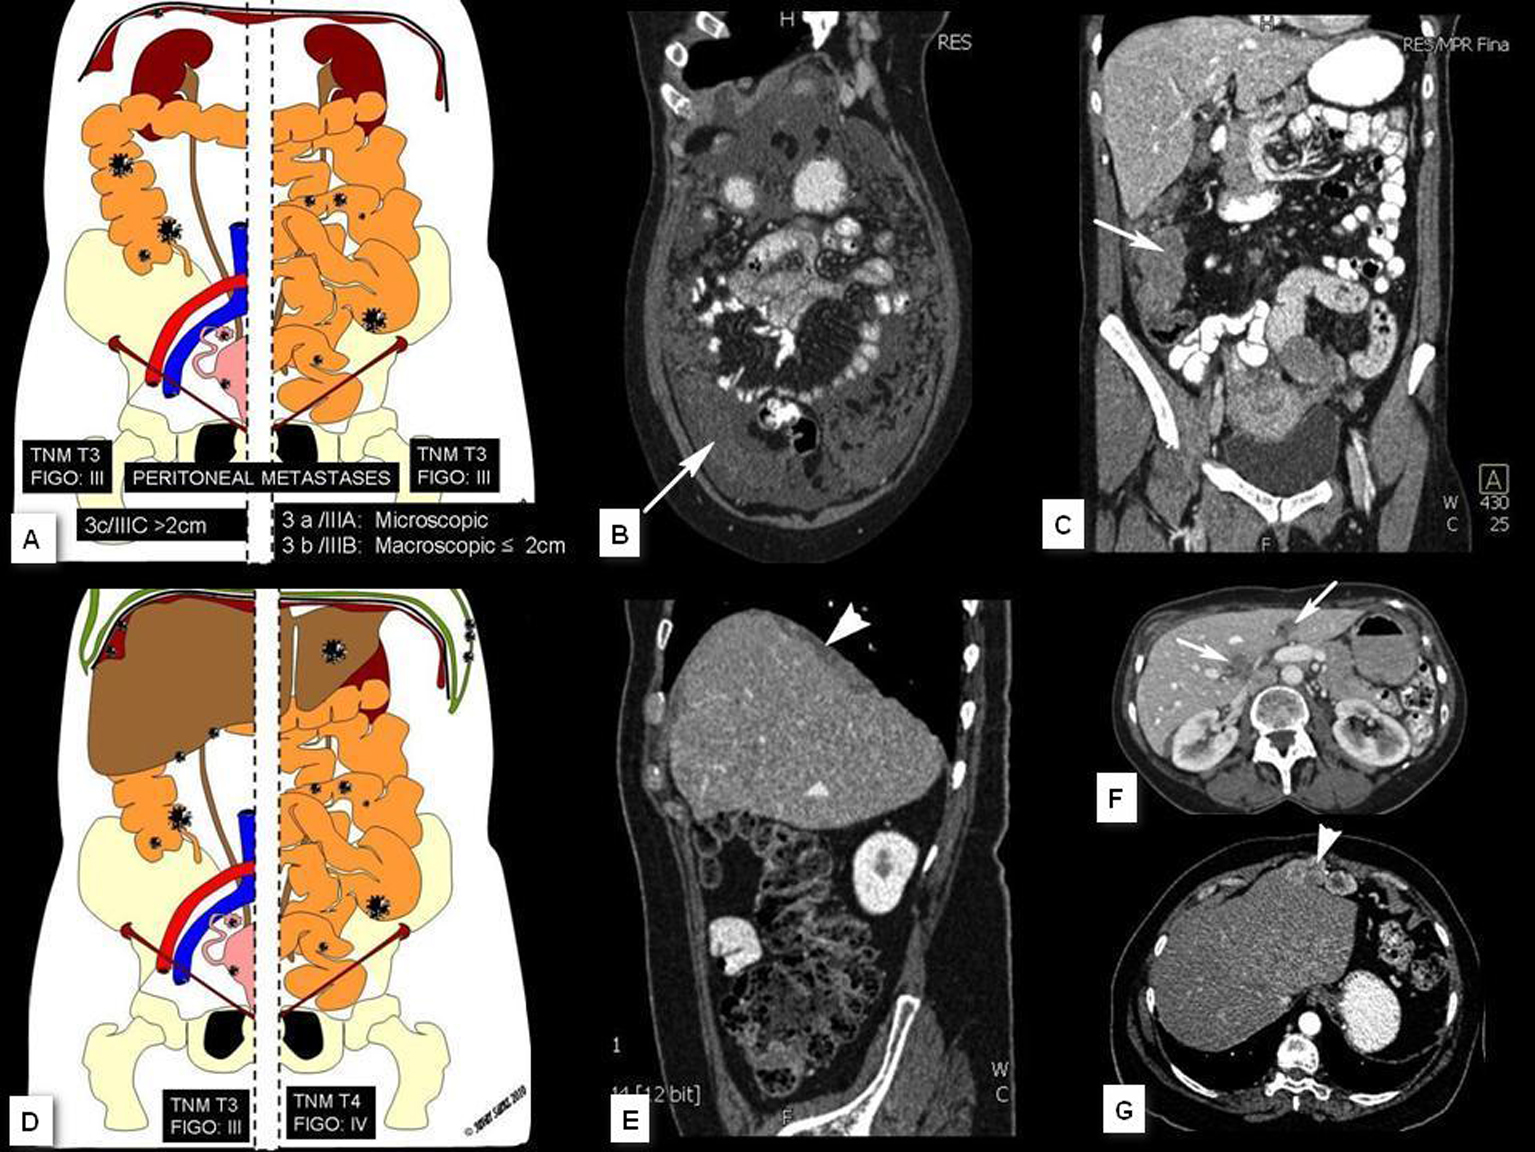

En el contexto del abordaje multidisciplinar para el diagnóstico y tratamiento del cáncer de ovario, la aportación del radiólogo incluye cuatro puntos fundamentales que son: identificación de la lesión, caracterización, estudio de extensión y valoración evolutiva. En el presente trabajo se describen los hallazgos y claves diagnósticas en TCMD (Tomografía Computarizada multidetector) y RM (Resonancia Magnética), la aportación e indicación de otras tecnologías como el PET (Tomografía por Emisión de Positrones) y se esbozan las técnicas emergentes basadas en imagen funcional (estudios dinámicos con contraste en RM y estudios de difusión por RM).Descargas

10. PANNU HK, BRISTOW RE, MONTZ FJ, FISHMAN EK. Multidetector CT of peritoneal carcinomatosis from ovarian cancer. Radiographics 2003; 23: 687-701.

12. WOODWARD PJ, HOSSEINZADEH K, SAENGER JS. From the archives of the AFIP. Radiologic staging of ovarian carcinoma with patologic correlation. Radiographics 2004; 24: 225-246.